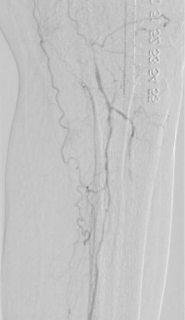

1. 术前造影:

2. 经鞘置入椎管、CXI、V18导丝正向开通股浅动脉下段,导丝通过,导管无法跟进,经皮穿刺钙化灶,导管跟进造影发现位于内膜下。

3. 经皮穿刺胫前动脉上段,置入新V18导丝,跟进CXI,与正向的椎管双向会师,建立导丝通路,予以3.0球囊预扩张。